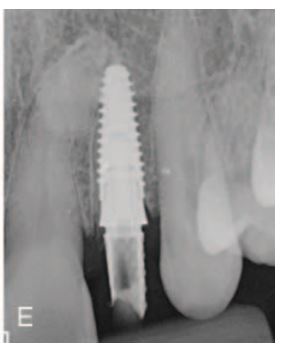

This patient presents with periimplantitis of the lower left quadrant. Removal of existing implants with Guided Bone Regeneration is required. The tent pole technique for GBR was used.